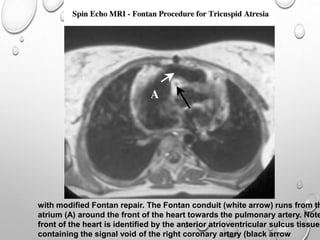

with modified Fontan repair. The Fontan conduit (white arrow) runs from th

atrium (A) around the front of the heart towards the pulmonary artery. Note

front of the heart is identified by the anterior atrioventricular sulcus tissue

containing the signal void of the right coronary artery (black arrow

with modified Fontanrepair. The Fontan conduit (white arrow) runs from th atrium (A) around the front of the heart towards the pulmonary artery. Note front of the heart is identified by the anterior atrioventricular sulcus tissue containing the signal void of the right coronary artery (black arrow